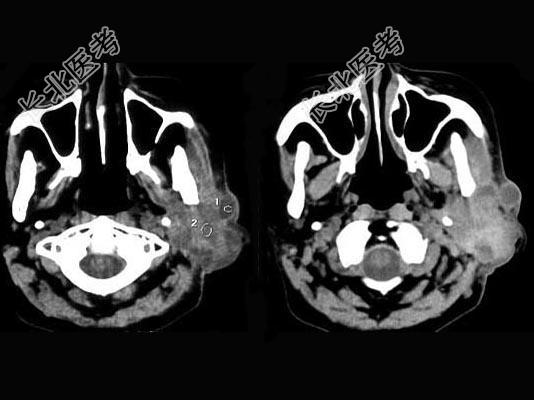

- 单项选择题女,55岁, 鼻咽癌放疗15年,近1周左耳根部肿胀, 无发热,PE: 左耳根部皮下扪及三个结节,有波动感和轻压痛, CT如图所示,最可能的诊断是 ( )

A、左腮腺腺瘤

B、左腮腺混合瘤

C、左腮腺腺淋巴瘤

D、左腮腺恶性混合瘤

E、左腮腺蜂窝织炎